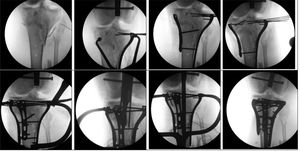

Group 2 (n=8. 33%): Two patients underwent surgery for both fractures using a single implant; an intramedullary nail. The remaining 6 patients underwent surgery using a combination of different implants. Four patients were treated at the level of the tibial plateau with plates and 2 patients with cannulated screws. At the level of the diaphysis, 3 patients were treated with an intramedullary rod, 3 patients with plates and one patient with a circular external fixator (Fig. 5).

Group 3 (n=10. 42%): Nine patients underwent surgery for both fractures using 2 implants and one patient underwent surgery using one implant. Eight patients underwent surgery using a T2 intramedullary rod at the diaphysis level and 2 patients underwent surgery using plates. At the distal level for the pilon (3 patients), one patient underwent surgery using a T2 and 2 patients underwent surgery using plates. At the ankle level (7 patients), 4 patients underwent surgery using cannulated screws, 2 patients underwent surgery using plates and one patient had conservative treatment (Table 2 and Fig. 6).